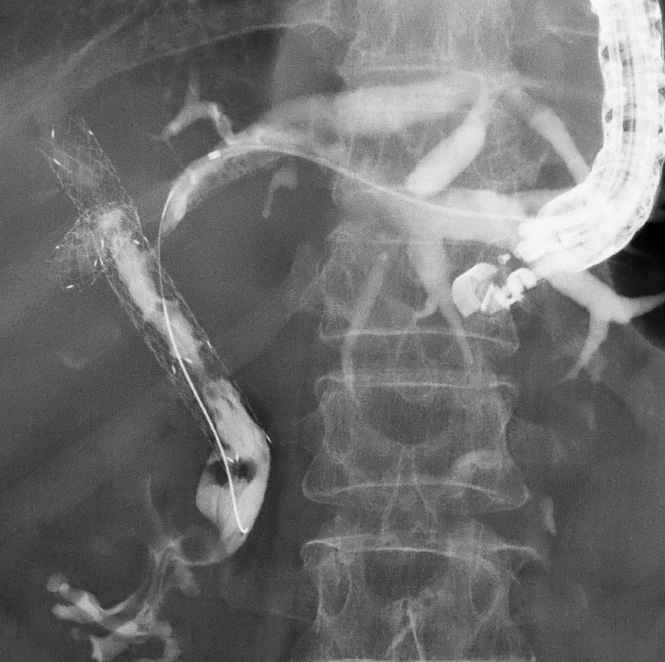

肝門部胆管癌に対するEUS下胆道ドレナージ